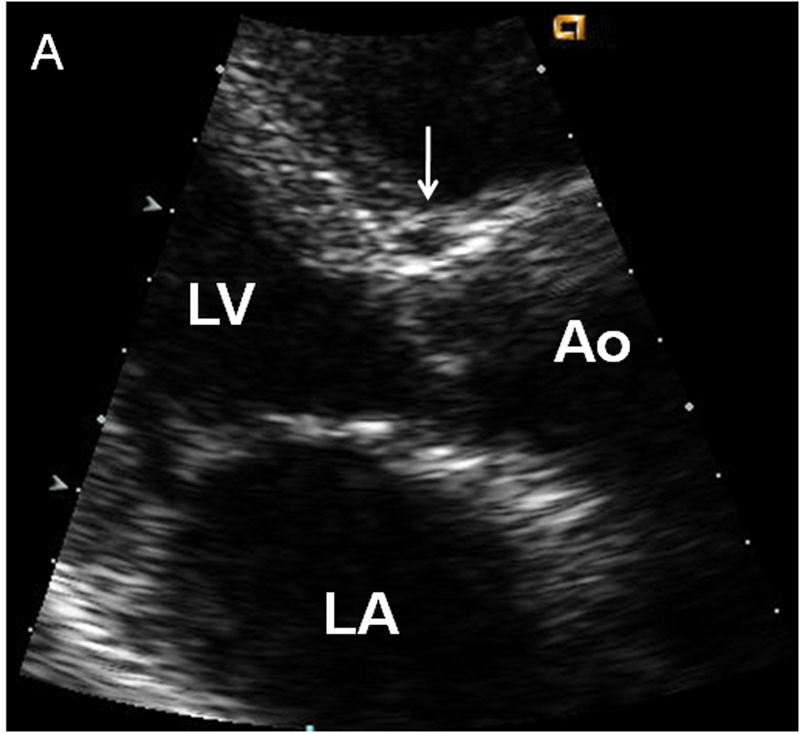

فحوصات تشخيصية لبعض امراض القلب والشرايين التاجية